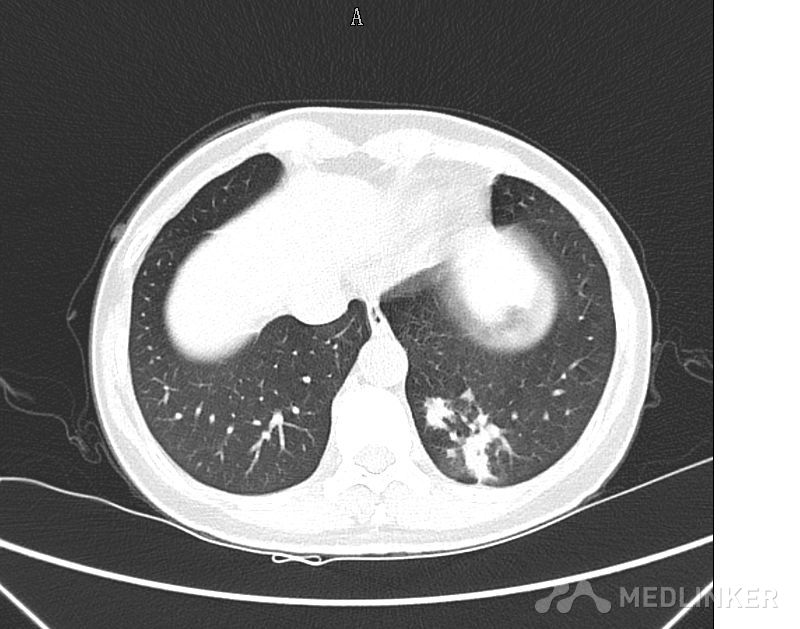

大家看看这个肺部的占位可能是什么?

肺部肿物

以CT图片为准,中年男性,反复咳嗽半个月入院,有低热,痰不多,无咯血,饮食睡眠正常。